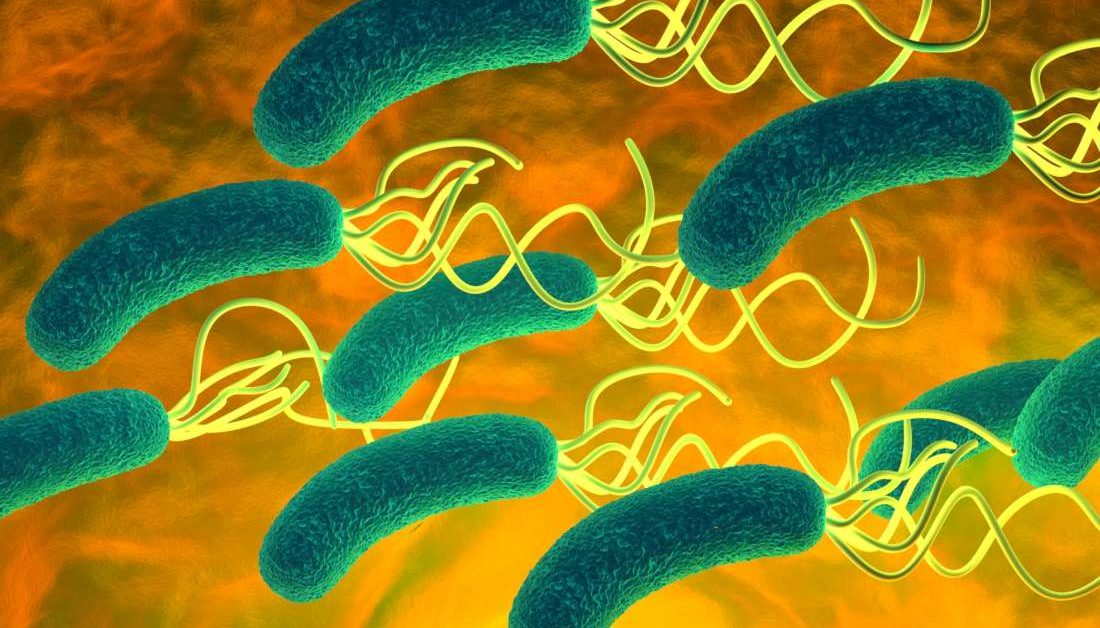

Кампилобактер фетус: патогенез и инфекции

/evrimagaci.org%2Fpublic%2Fcontent_media%2Fb099374a4578fc241a0555a594831216.jpeg)